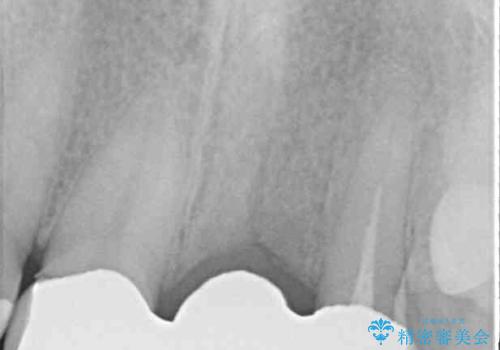

- 保険診療の前歯のブリッジが、形態も色も不自然で気になるとのことで来院された患者様です。

神経の抜かれている土台の歯は根管治療を行った上で、オールセラミックブリッジにより補綴することとしました。